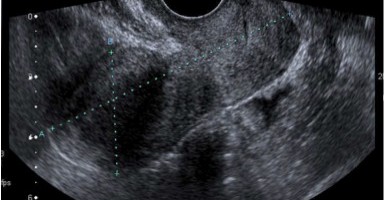

Sebbene l’ecografia sia utilizzata, prevalentemente, appoggiando la sonda sulla superficie esterna del corpo, talora è necessario introdurla all’interno per studiare organi che sarebbero mal distinguibili da fuori.

Per questo sono state disegnate sonde di forma adatta per essere messe nella cavità rettale, attraverso l’ano, al fine di indagare la prostata e le pareti dell’ultima parte dell’intestino (Ecografia Trans-rettale) o, nella vagina (Trans-vaginale), per esplorare l’apparato genitale femminile.

Più recentemente si sono affermate tecniche che, facendo penetrare la sonda ancora più in profondità, per esempio nell’esofago e nello stomaco, permettono di scrutare da vicino molti organi nel torace e nell’addome e forniscono immagini con dettagli molto precisi.